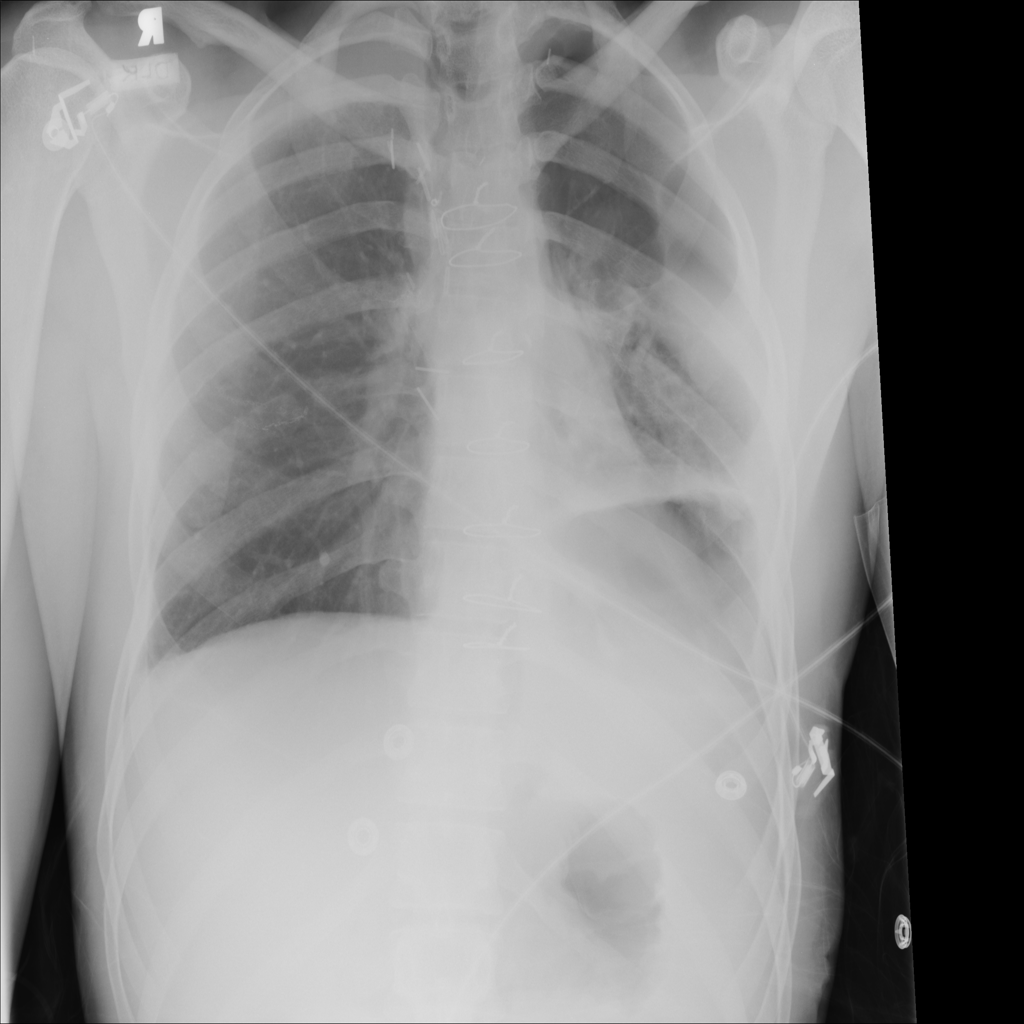

PAT-4639 · IMG-020Pneumothorax

PAT-4639 · IMG-020

PA